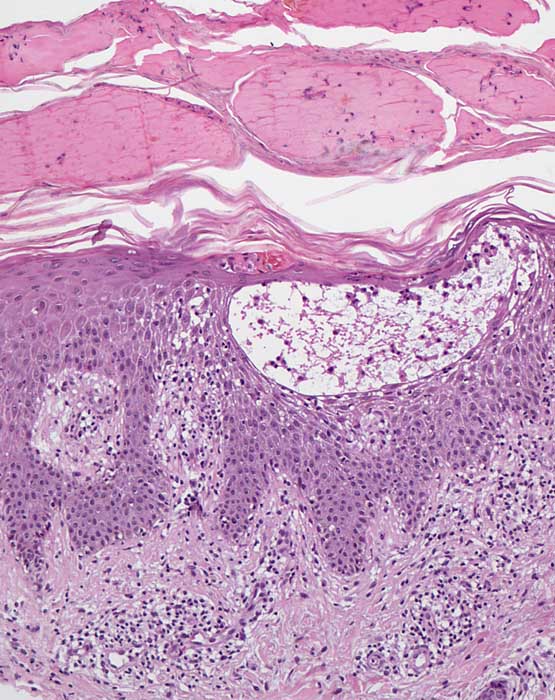

Asteatotisches Ekzem/Dermatitis asteatotica Wikiderm.de